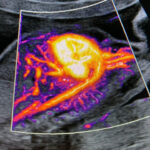

La caratteristica della tecnologia tridimensionale consiste nel fatto che non si lavora su un piano ma su un volume. Pertanto è possibile non solo, esaminare un determinato distretto nelle tre dimensioni, ma di manipolare sui tre piani il volume immagazzinato, consentendo di mettere in evidenza strutture anatomiche altrimenti difficilmente evidenziabili. Pertanto il 3D e il 4D non viene utilizzato esclusivamente per visualizzare il visino del feto* e le parti superficiali come le mani e i piedi ma per studiare il cervello (neurosonografia)**, l’apparato scheletrico *** e quello cardiocircolatorio****.